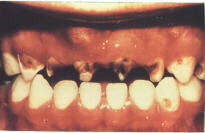

Severe Baby Bottle Tooth Decay

The teeth most likely to be damaged are the upper front teeth. They are some of the first teeth to erupt and thus have the longest exposure time to the sugars in the bottle. The lower front teeth tend to be protected by the tongue as the child sucks on the nipple of the bottle or the breast.